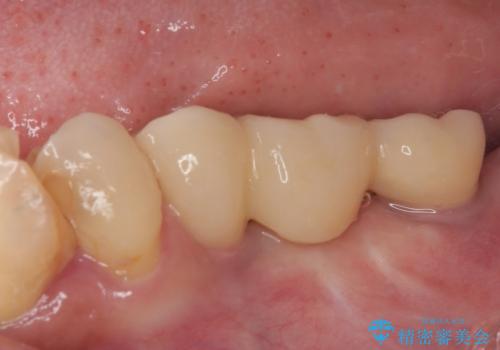

放置していたむし歯 抜歯即時埋入インプラントによる補綴治療

左下小臼歯は根管治療で対応する予定でしたが、診断のために歯肉を開いたところ頬側に垂直破折が認められたため、抜歯即時埋入インプラントによる補綴治療を選択することとしました。

右下は大臼歯部の歯は抜歯即時埋入インプラントにて、手前の歯は保存して補綴治療を行うこととしました。

インプラント埋入時に十分な安定値を得ることができたため、速やかに仮歯を装着し、最小限の通院回数で治療を終えることができました。